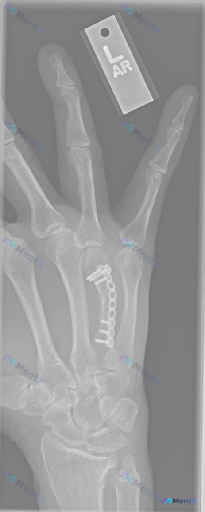

整理到一张左手正位X光片的术后复查资料,标注“L”,覆盖掌骨、近端指骨及部分腕关节。 先把看到的几个点列出来: 1. 第3掌骨有钢板+多枚螺钉固定,形态和骨干弧度基本匹配 2. 第3掌骨干能看到透亮线 3. 透亮线附近有模糊的骨痂影 4. 周围软组织没看到明显肿胀,也没肿块或钙化 5. 掌指、指间关...